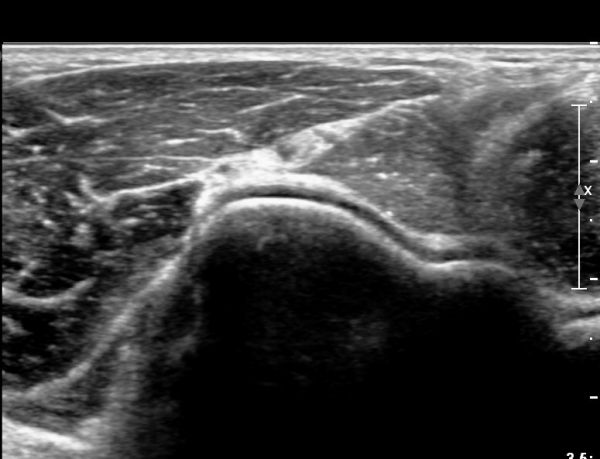

ŽÃËÀÚ¸¦ ¸»´ÜÀ¸·Î Á¶±Ý À̵¿ÇÏ´Ï Èİñ°£ ½Å°æÀÌ ÀÛ¾ÆÁö°í(»çÁø 2),

ŽÃËÀÚ¸¦ Á¶±Ý ´õ À̵¿ÇÏ´Ï Èİñ°£ ½Å°æÀÇ ºÎÁ¾ÀÌ ´Ù½Ã °üÂûµÈ´Ù(»çÁø 3).